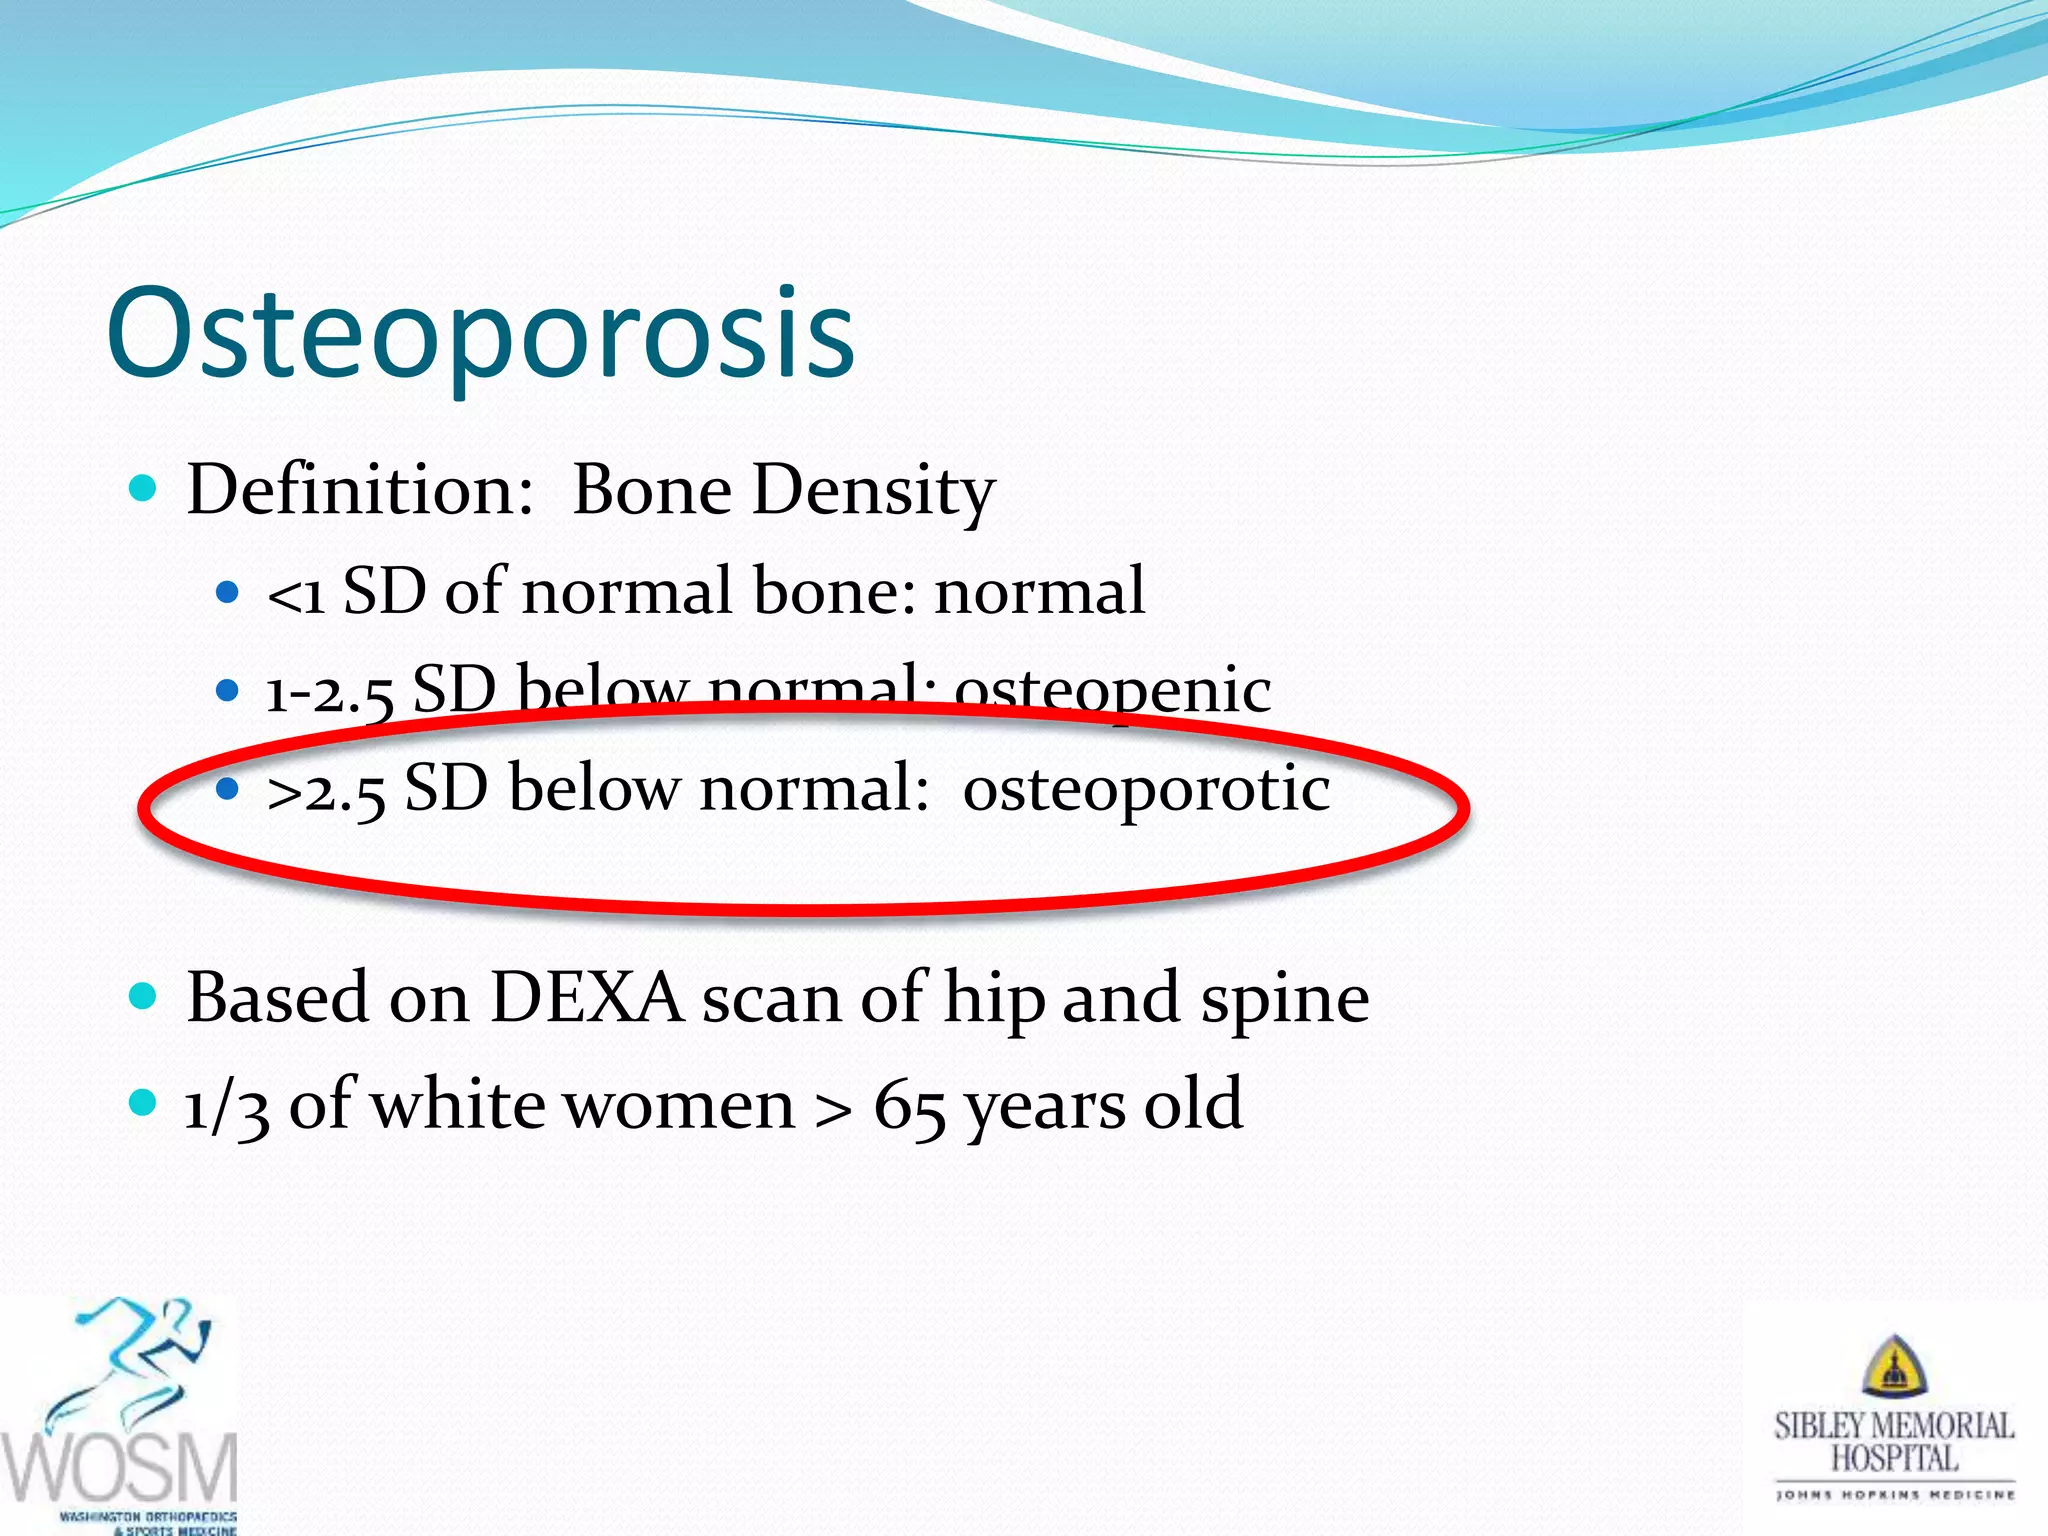

This document discusses wrist fractures, including who is most at risk, common causes, signs and symptoms, treatment options, and prevention. The elderly and those with osteoporosis are most prone to wrist fractures due to falls. Treatment may involve splinting, casting, closed reduction, or surgery depending on the fracture. Maintaining bone health through medication, vitamins, exercise, and diet can help prevent wrist fractures.